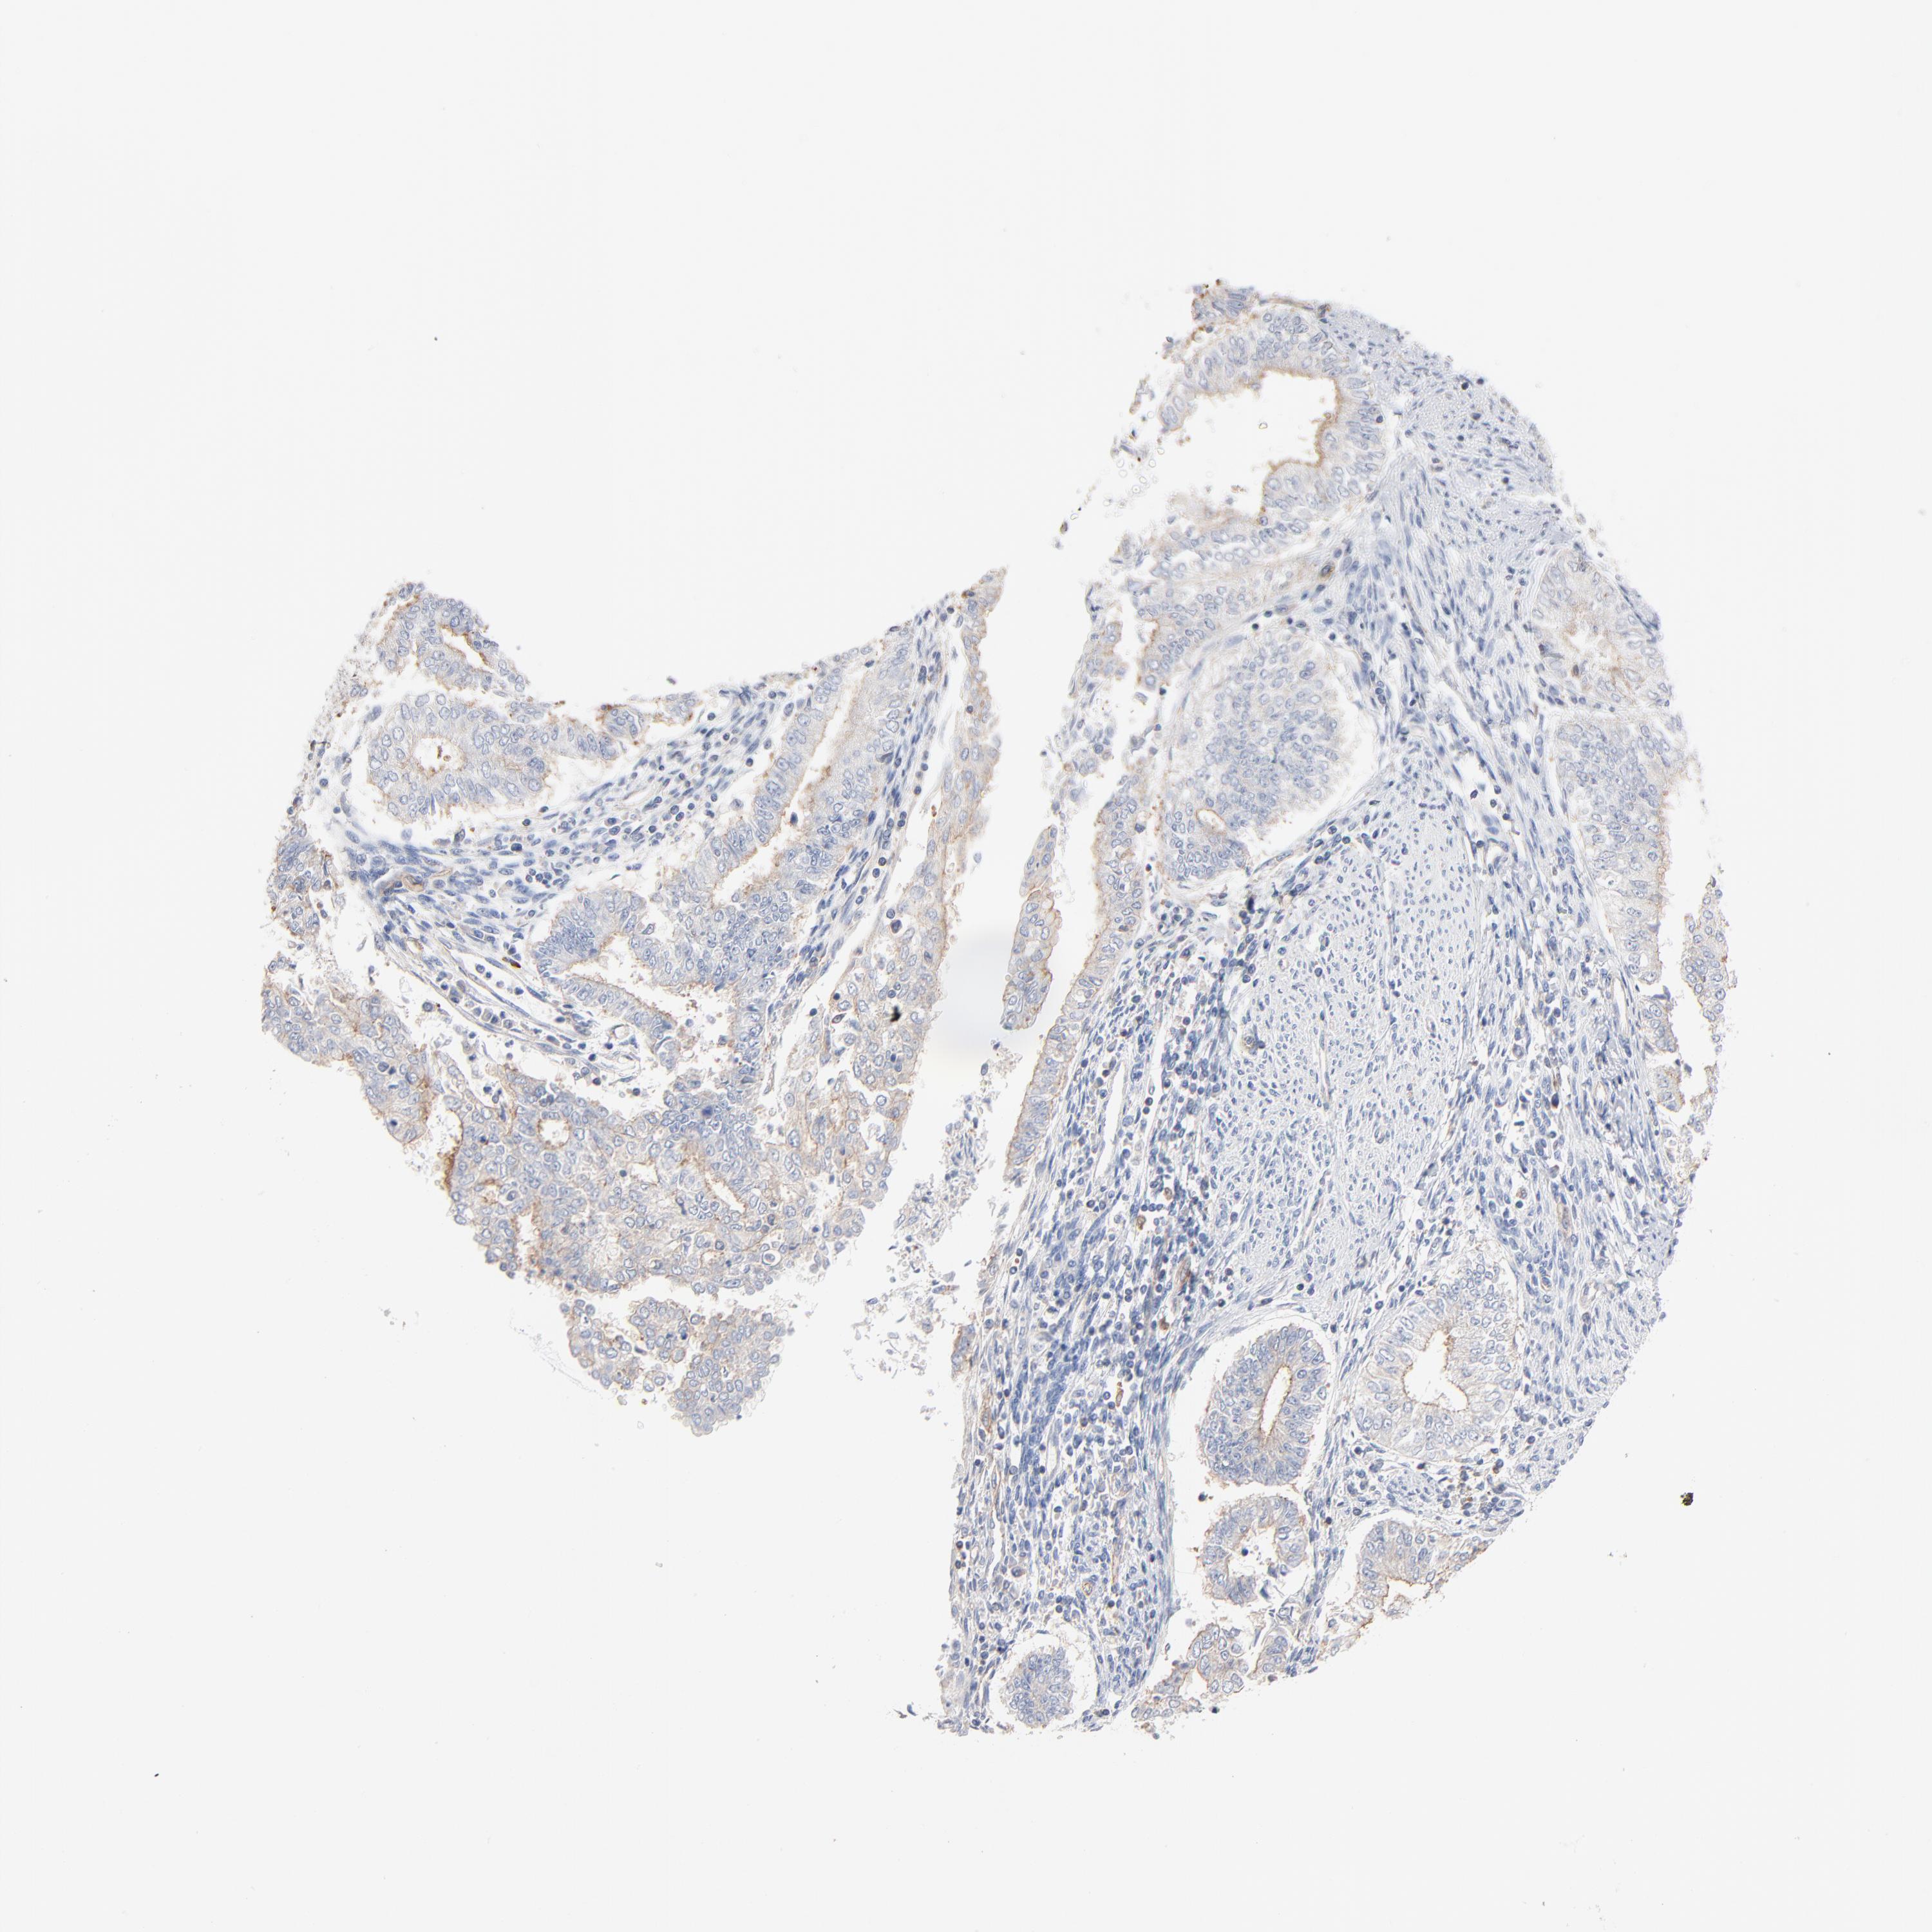

ENDOMETRIAL CANCER - Protein expressioni

A mouse-over function shows sample information and annotation data. Click on an image to view it in a full screen mode. Samples can be filtered based on level of antibody staining by selecting one or several of the following categories: high, medium, low and not detected. The assay and annotation is described here.

Note that samples used for immunohistochemistry by the Human Protein Atlas do not correspond to samples in the TCGA dataset.

Antibody stainingi

Antibody staining in the annotated cell types in the current human tissue is reported as not detected, low, medium, or high, based on conventional immunohistochemistry profiling in selected tissues. This score is based on the combination of the staining intensity and fraction of stained cells.

Each image is clickable and will lead to virtual microscopy that enables deeper exploration of all samples and also displays staining intensity scores, fraction scores and subcellular localization as well as patient and tissue information for each sample.

Antibody HPA003578

Staining

High

Medium

Low

Not detected

Intensity

Strong

Moderate

Weak

Negative

Quantity

>75%

75%-25%

<25%

None

Location

Nuclear

Cytoplasmic/membranous

Cytoplasmic/membranous,nuclear

Adenocarcinoma, NOS

Neoplasm, malignant, NOS